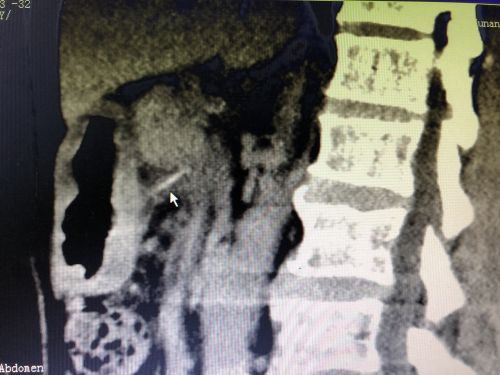

影像资料上可以看到胃里的异物(鼠标所示)。

69岁的刘大爷是湖南娄底人,2019年4月初,平时身体棒棒的老人出现上腹部隐隐作痛的情况,以为是感冒后肠胃不适,吃了点感冒药后就没当回事。到了9月中旬,老人再次出现上腹部疼痛不适,到当地医院做了个胃镜,结果让人大吃一惊——一根牙签横插在胃里,将胃戳出两个洞!